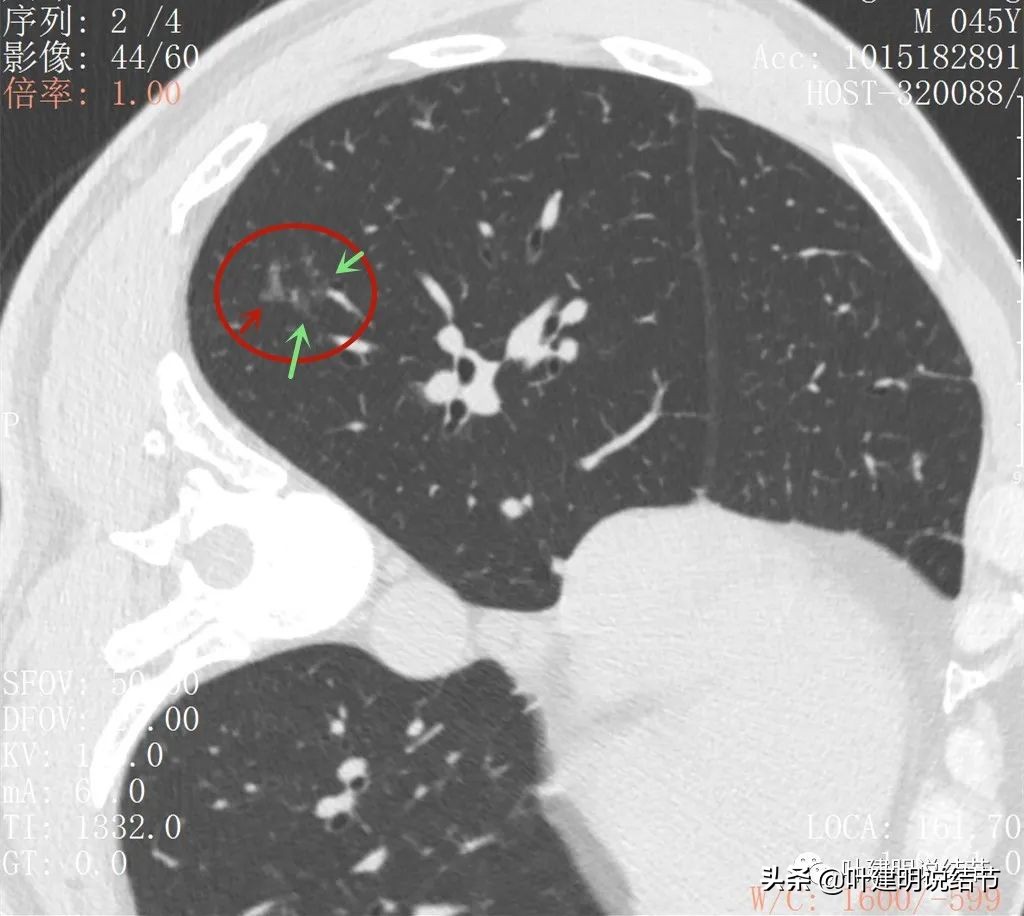

2022年5月复查靶扫描的图像:

病灶出现,磨玻璃密度,非圆形或类圆形,感觉比较散

病灶虽然不密,但轮廓较清,磨玻璃成分明显,感觉偏向恶性

病灶有少许实性成分(粉色箭头)

病灶似有血管进入(桔色箭头),而且血管异常增粗,整体病灶轮廓较清,似有分叶,中间有空泡征呈蜂窝状

病灶内部见血管穿行,轮廓与瘤肺边界清楚

扩张的细支气管感觉较为僵硬

少许区域有密度较高的部分,扩张细支气管明显,且显僵硬

病灶较散在

病灶形态不规则,不是圆形或类圆形

此层见病灶边缘显糊

病灶显模糊,感觉过于散在了些

病灶形散,密度低

这样的靶扫描影像,感觉较平扫与薄层扫描来看恶性的可能性有所加大,但不太符合的一是整体看上去没有聚拢性,过于散了点;二是有形成分相对偏少,细支气管扩张的区域较大;三是虽有些层面瘤肺边界与轮廓清,但也有的层面显糊,不太像一般磨玻璃为表现肺癌的样子。但要除外恶性是万万不能的。所以我当时考虑6成的可能是恶性,4成可能是良性。可是如果真恶性,这样的病灶有血管穿行也有病灶边缘区域异常增粗血管,长径超过2厘米,已经随访过3个多月了,口服抗炎没有吸收好转(慢性炎抗炎一般不会有用)。是存在一定风险的。所以再请影像科同事进行了图像后处理重建。